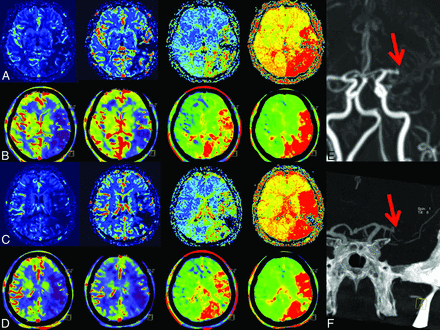

2) Case example. In rows A and C, MRP; in B and D, corresponding FD-CTP parameters maps (left to right: CBF, CBV, MTT, and TTP) are displayed. A and B and C and D are corresponding MRP and FD-CTP images. Due to an MCA occlusion, there is a significant perfusion deficit in the CBF, MTT, and TTP maps. There is no significant CBV lesion in this patient. The MCA occlusion was visible in either the MRA (E, red arrow) or in FD-CTA (F, red arrow) MIP reconstruction. The green arrow indicates a small temporal branch.